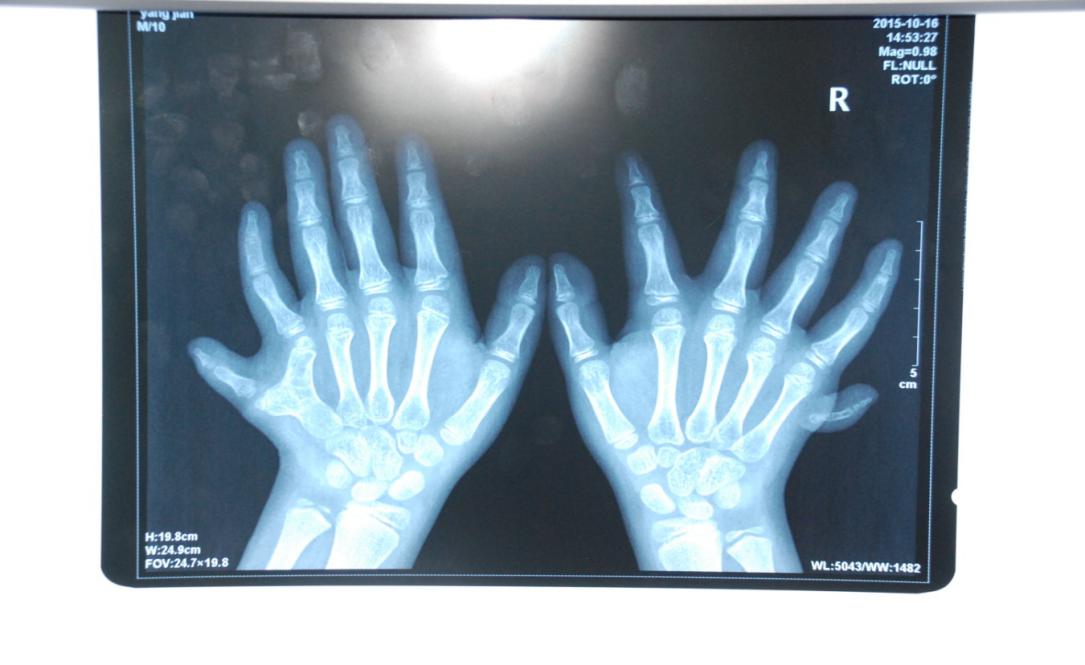

廈門(mén)眼科中心小兒眼科修陽(yáng)暉博士在日常的診療過(guò)程中就接診了不少這樣的的特殊家庭,讓其尤為印象深刻的就是一年前接診的BBS綜合征患者。當(dāng)時(shí)來(lái)院就診的是一對(duì)親兄弟,之前已在多家醫(yī)院做過(guò)檢查,因其均有較大散光和斜視,肉眼下眼底檢查未見(jiàn)異常,故外院均診斷為弱視,這也符合眼科門(mén)診常規(guī)的診斷邏輯與思維。但由于兄弟倆均有智力發(fā)育遲緩、特殊面容及四肢均有六指和六趾的特異體征引起了修陽(yáng)暉博士的警覺(jué):會(huì)不會(huì)是一種特殊遺傳性疾病或綜合征?后續(xù)的檢查結(jié)果進(jìn)一步證實(shí)了修陽(yáng)暉博士的懷疑---患兒均有夜盲,ERG、VEP及OCT檢查顯示雙眼的視網(wǎng)膜神經(jīng)上皮層結(jié)構(gòu)及功能均明顯異常。由于之前未遇到此種病例,修陽(yáng)暉博士在診斷一欄寫(xiě)下視網(wǎng)膜色素變性并打上了個(gè)問(wèn)號(hào),同時(shí)留下了病人的聯(lián)系方式。

BBS綜合征(Bardet-Biedl綜合征)是一種主要累及纖毛結(jié)構(gòu)與功能的罕見(jiàn)常染色體隱性遺傳性疾病。纖毛分布于哺乳動(dòng)物體內(nèi)的大多數(shù)細(xì)胞,它是一種廣泛存在于各種細(xì)胞表面的細(xì)胞器,體型微小但結(jié)構(gòu)復(fù)雜、作用強(qiáng)大,能感知細(xì)胞外機(jī)械和化學(xué)信號(hào)變化并協(xié)助其轉(zhuǎn)導(dǎo)到細(xì)胞內(nèi)部從而引起細(xì)胞應(yīng)答。高等動(dòng)物的視覺(jué)、觸覺(jué)、嗅覺(jué)、聽(tīng)覺(jué)的傳遞都依賴(lài)于體內(nèi)外正常的纖毛結(jié)構(gòu)和功能。因此BBS綜合征常累及全身多個(gè)系統(tǒng)和器官,在臨床上主要表現(xiàn)為:視網(wǎng)膜色素變性、智力發(fā)育異常、向心性肥胖、多指(趾)、性腺發(fā)育異常、腎臟異常。除此之外還有許多諸如:語(yǔ)言發(fā)育障礙、聽(tīng)力異常、嗅覺(jué)異常、斜視、白內(nèi)障、散光、牙齒發(fā)育異常、短指(趾)、并指(趾)、肝纖維化、糖尿病、高血壓等表現(xiàn)。